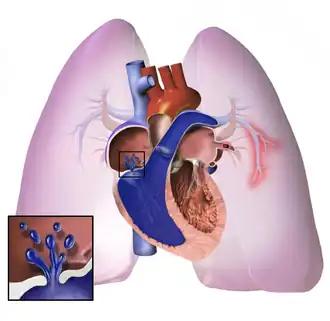

Fisiopatologia

O processo subjacente da hipertensão pulmonar varia e, com frequência, múltiplos fatores são responsáveis. Normalmente, o leito vascular pulmonar pode receber o volume sanguíneo liberado pelo ventrículo direito. Ele apresenta uma baixa resistência ao fluxo sanguíneo aumentado por meio da dilatação dos vasos na circulação pulmonar. Entretanto, se o leito vascular pulmonar está destruído ou obstruído, como na hipertensão pulmonar, a capacidade de receber qualquer fluxo ou volume do sangue fica prejudicada, e, então, o fluxo sanguíneo aumentado eleva a pressão da artéria pulmonar. À medida que a pressão da arterial pulmonar aumenta, também aumenta a resistência vascular pulmonar. A constrição da artéria pulmonar (como na hipoxemia ou hipercapnia) e a redução no leito vascular pulmonar (que ocorre com a embolia pulmonar) resultam em um aumento na resistência e pressão vasculares pulmonares. Essa carga de trabalho aumentada afeta a função ventricular direita. Por fim, o miocárdio não consegue satisfazer as demandas crescentes impostas a ele, levando à hipertrofia (aumento e dilatação) e insuficiência ventricular direita.